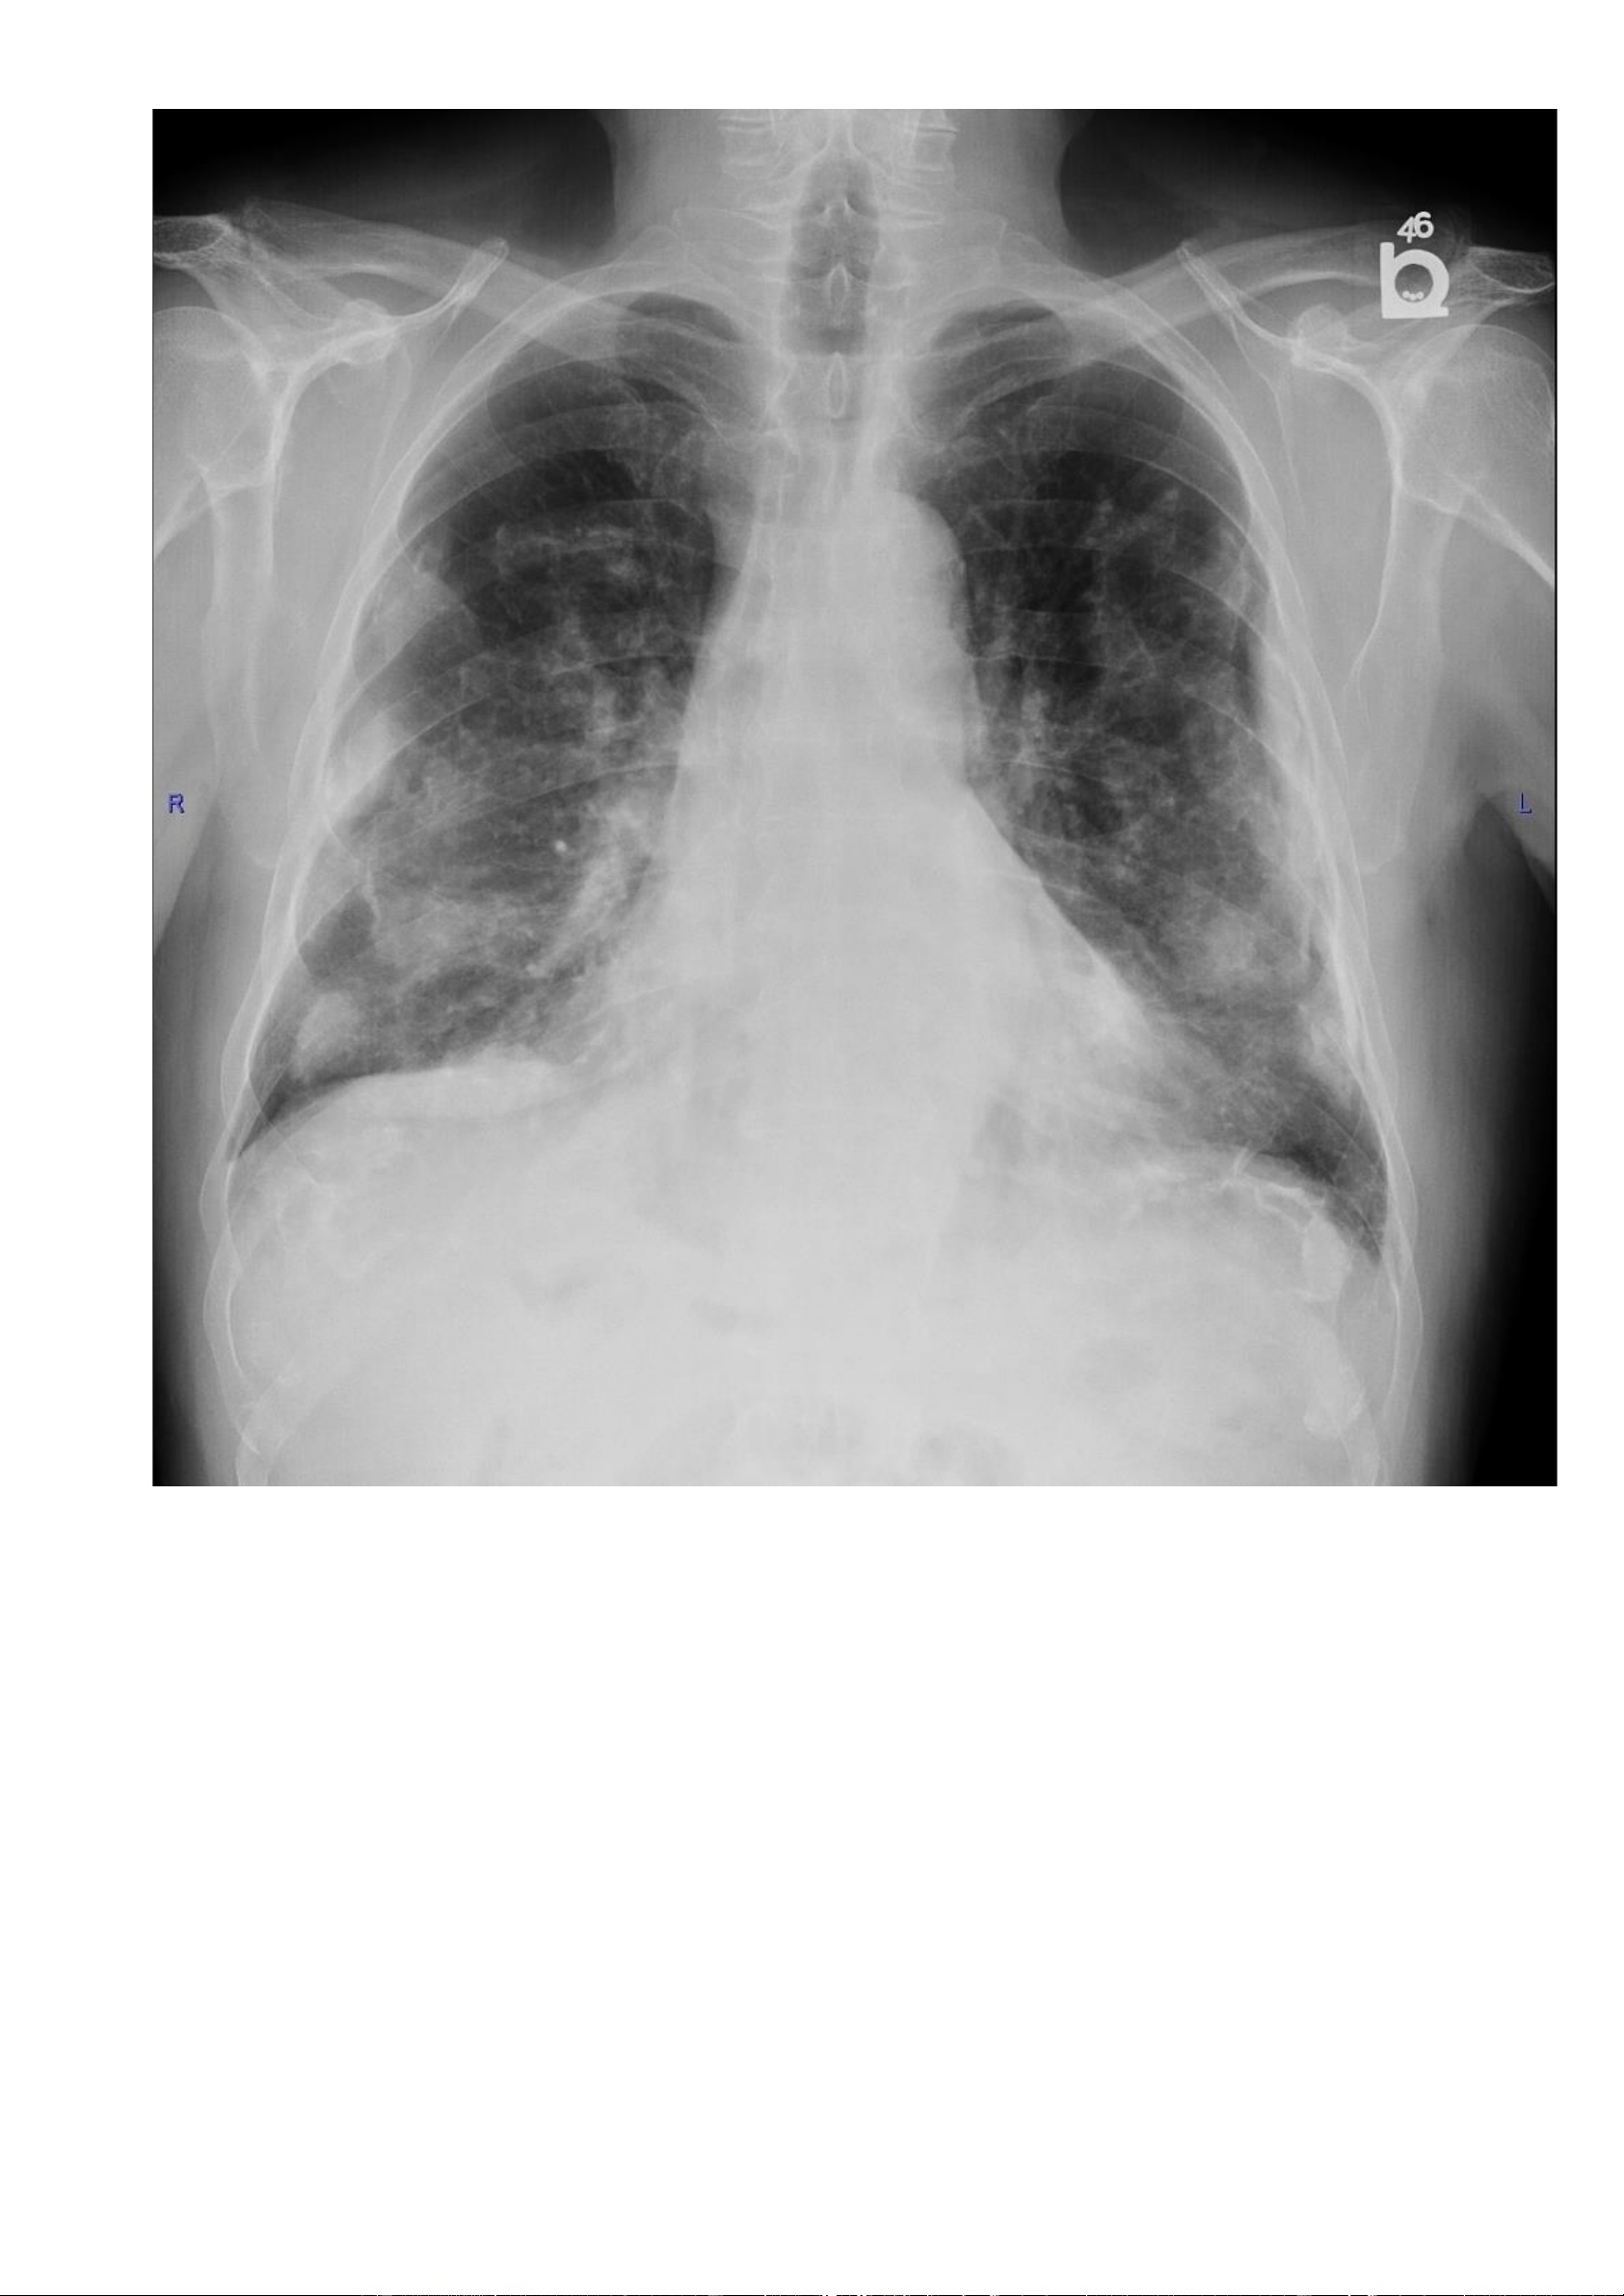

Nguồ https://radiopaedia.org/cases/calcified-pleural-plaques-4 -

nh nhân: Bệnh nhân nam, 75 tuổi, giảm chức năng phổi, tiền sử nghề nghiệp có liên quan đến amiăng. - Hình ả lOMoAR cPSD| 22014077 Phan Tùng Bách

Các mảng màng phổi vôi hoá hai bên. 7.7. Trư p 7: -